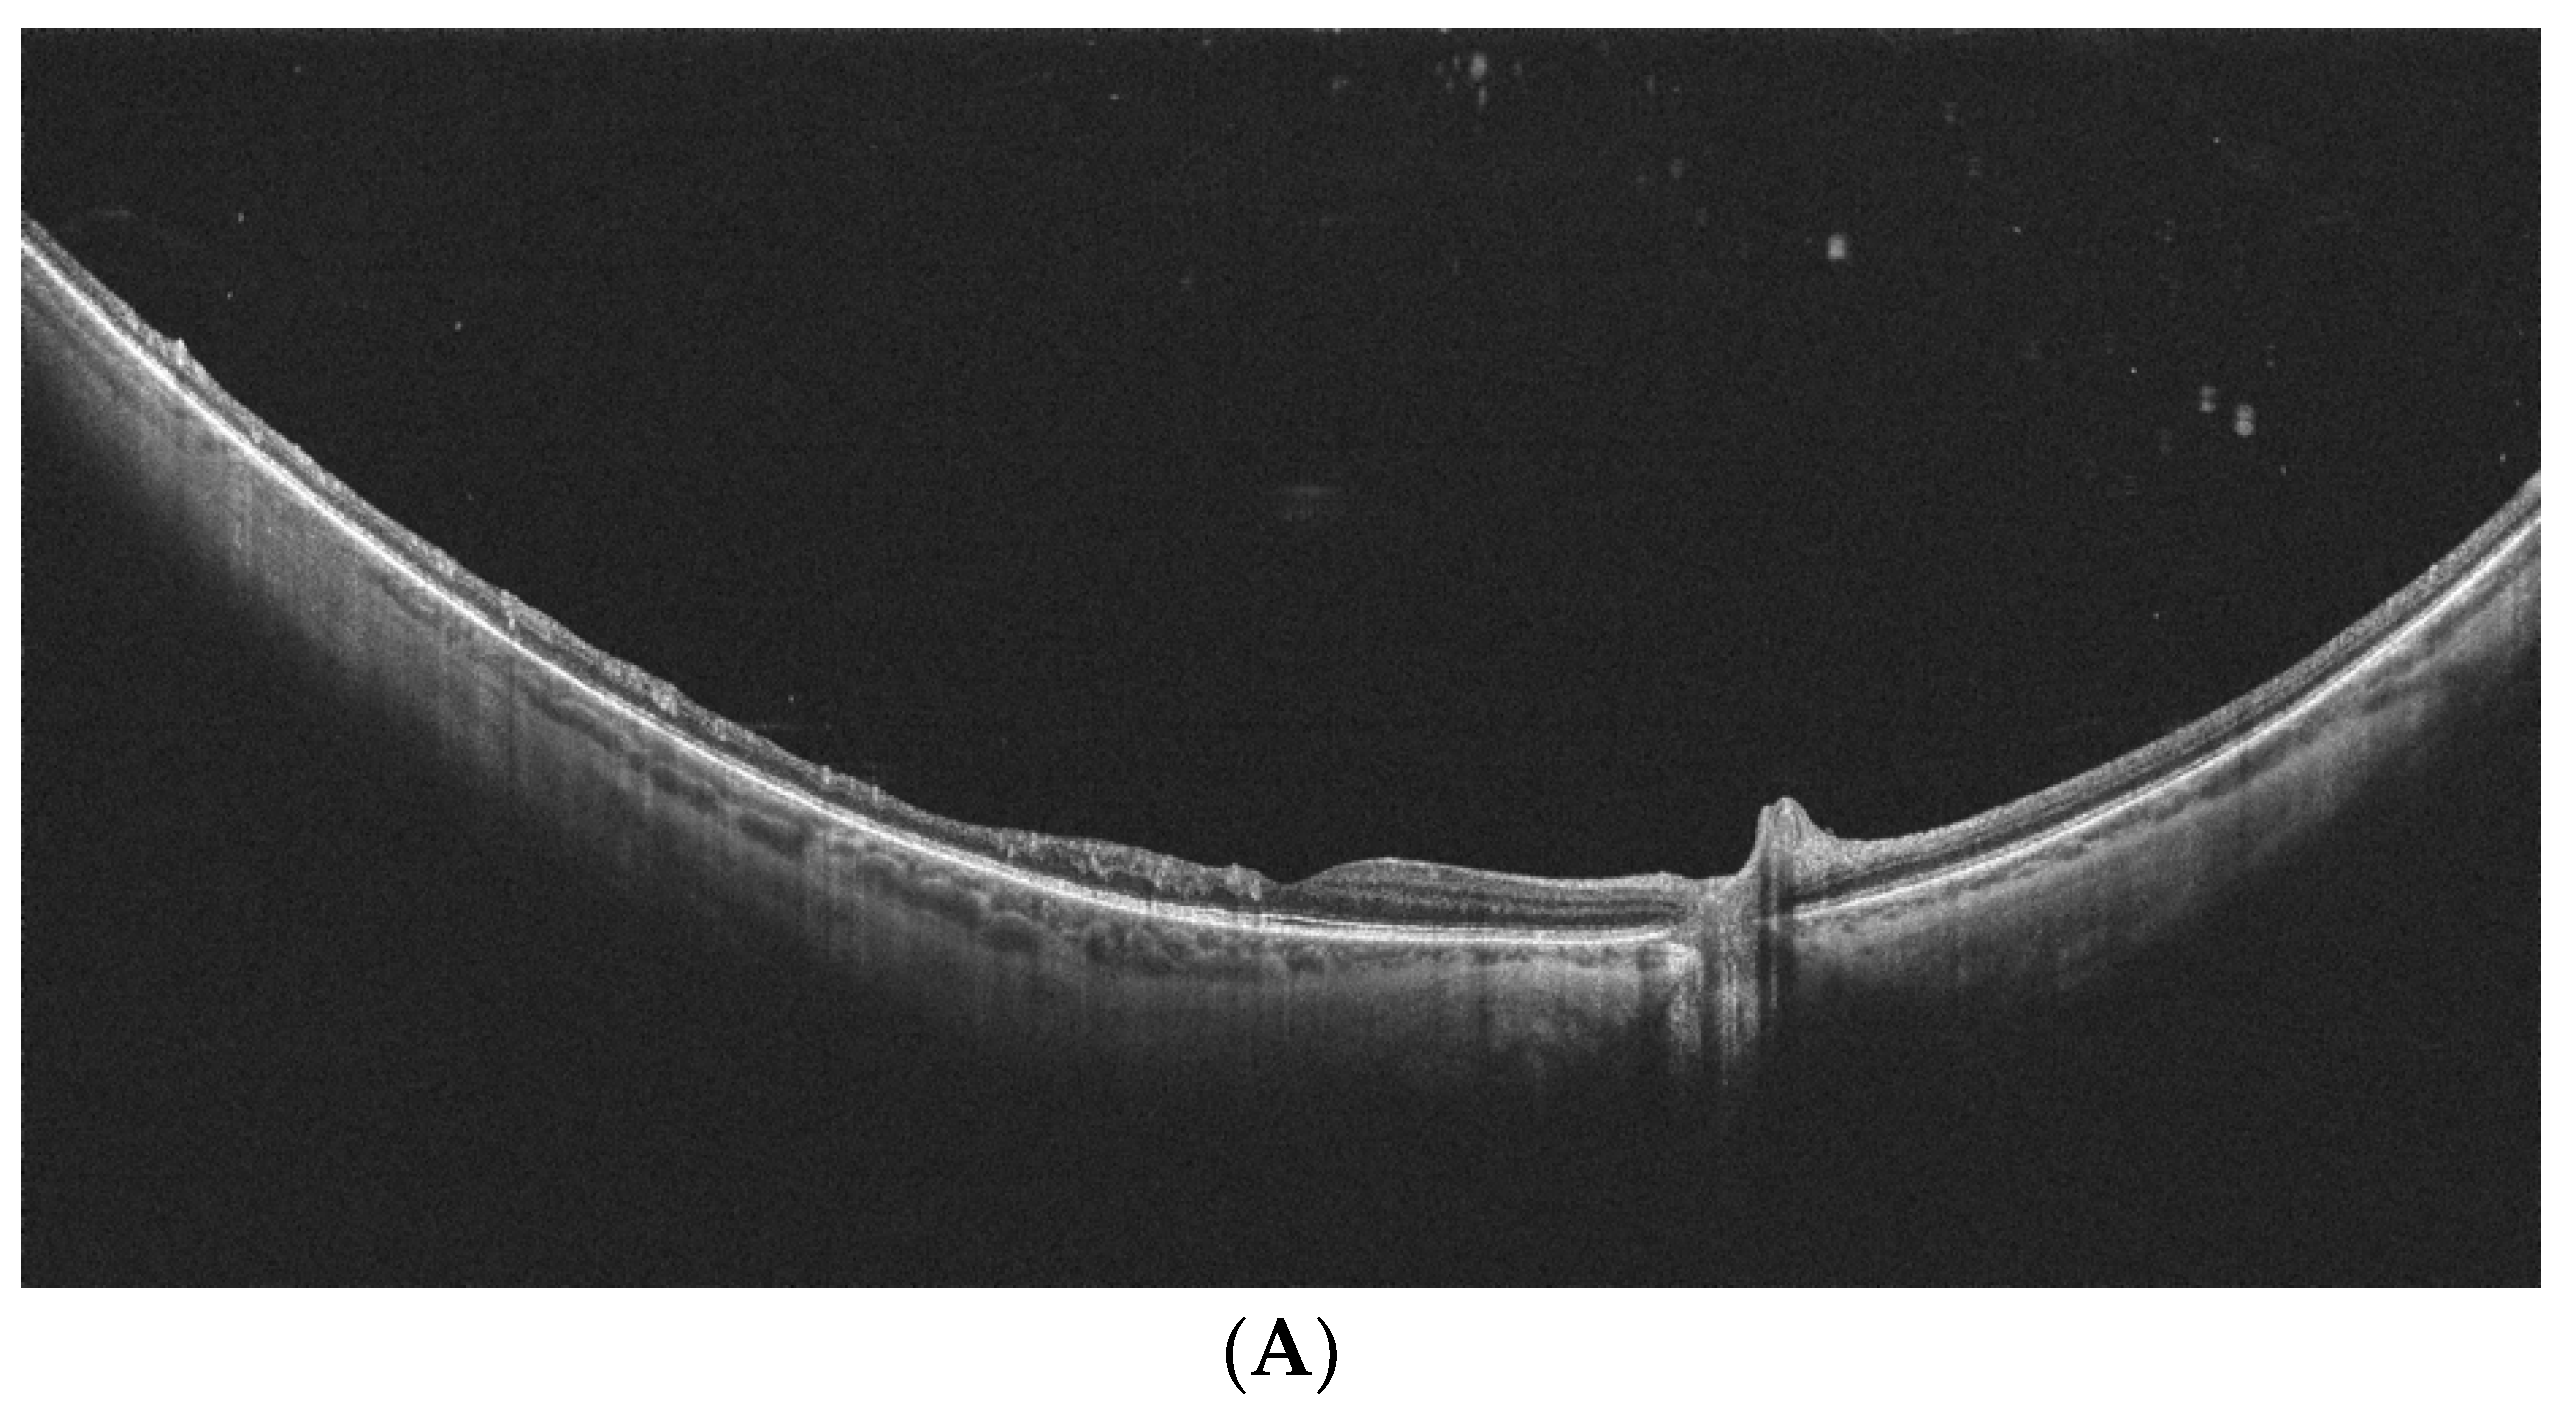

- Kurobe, R.; Hirano, Y.; Ogura, S.; Yasukawa, T.; Ogura, Y. Ultra-Widefield Swept-Source Optical Coherence Tomography Findings of Peripheral Retinal Degenerations and Breaks. Clin. Ophthalmol. 2021, 15, 4739–4745. [Google Scholar] [CrossRef] [PubMed]